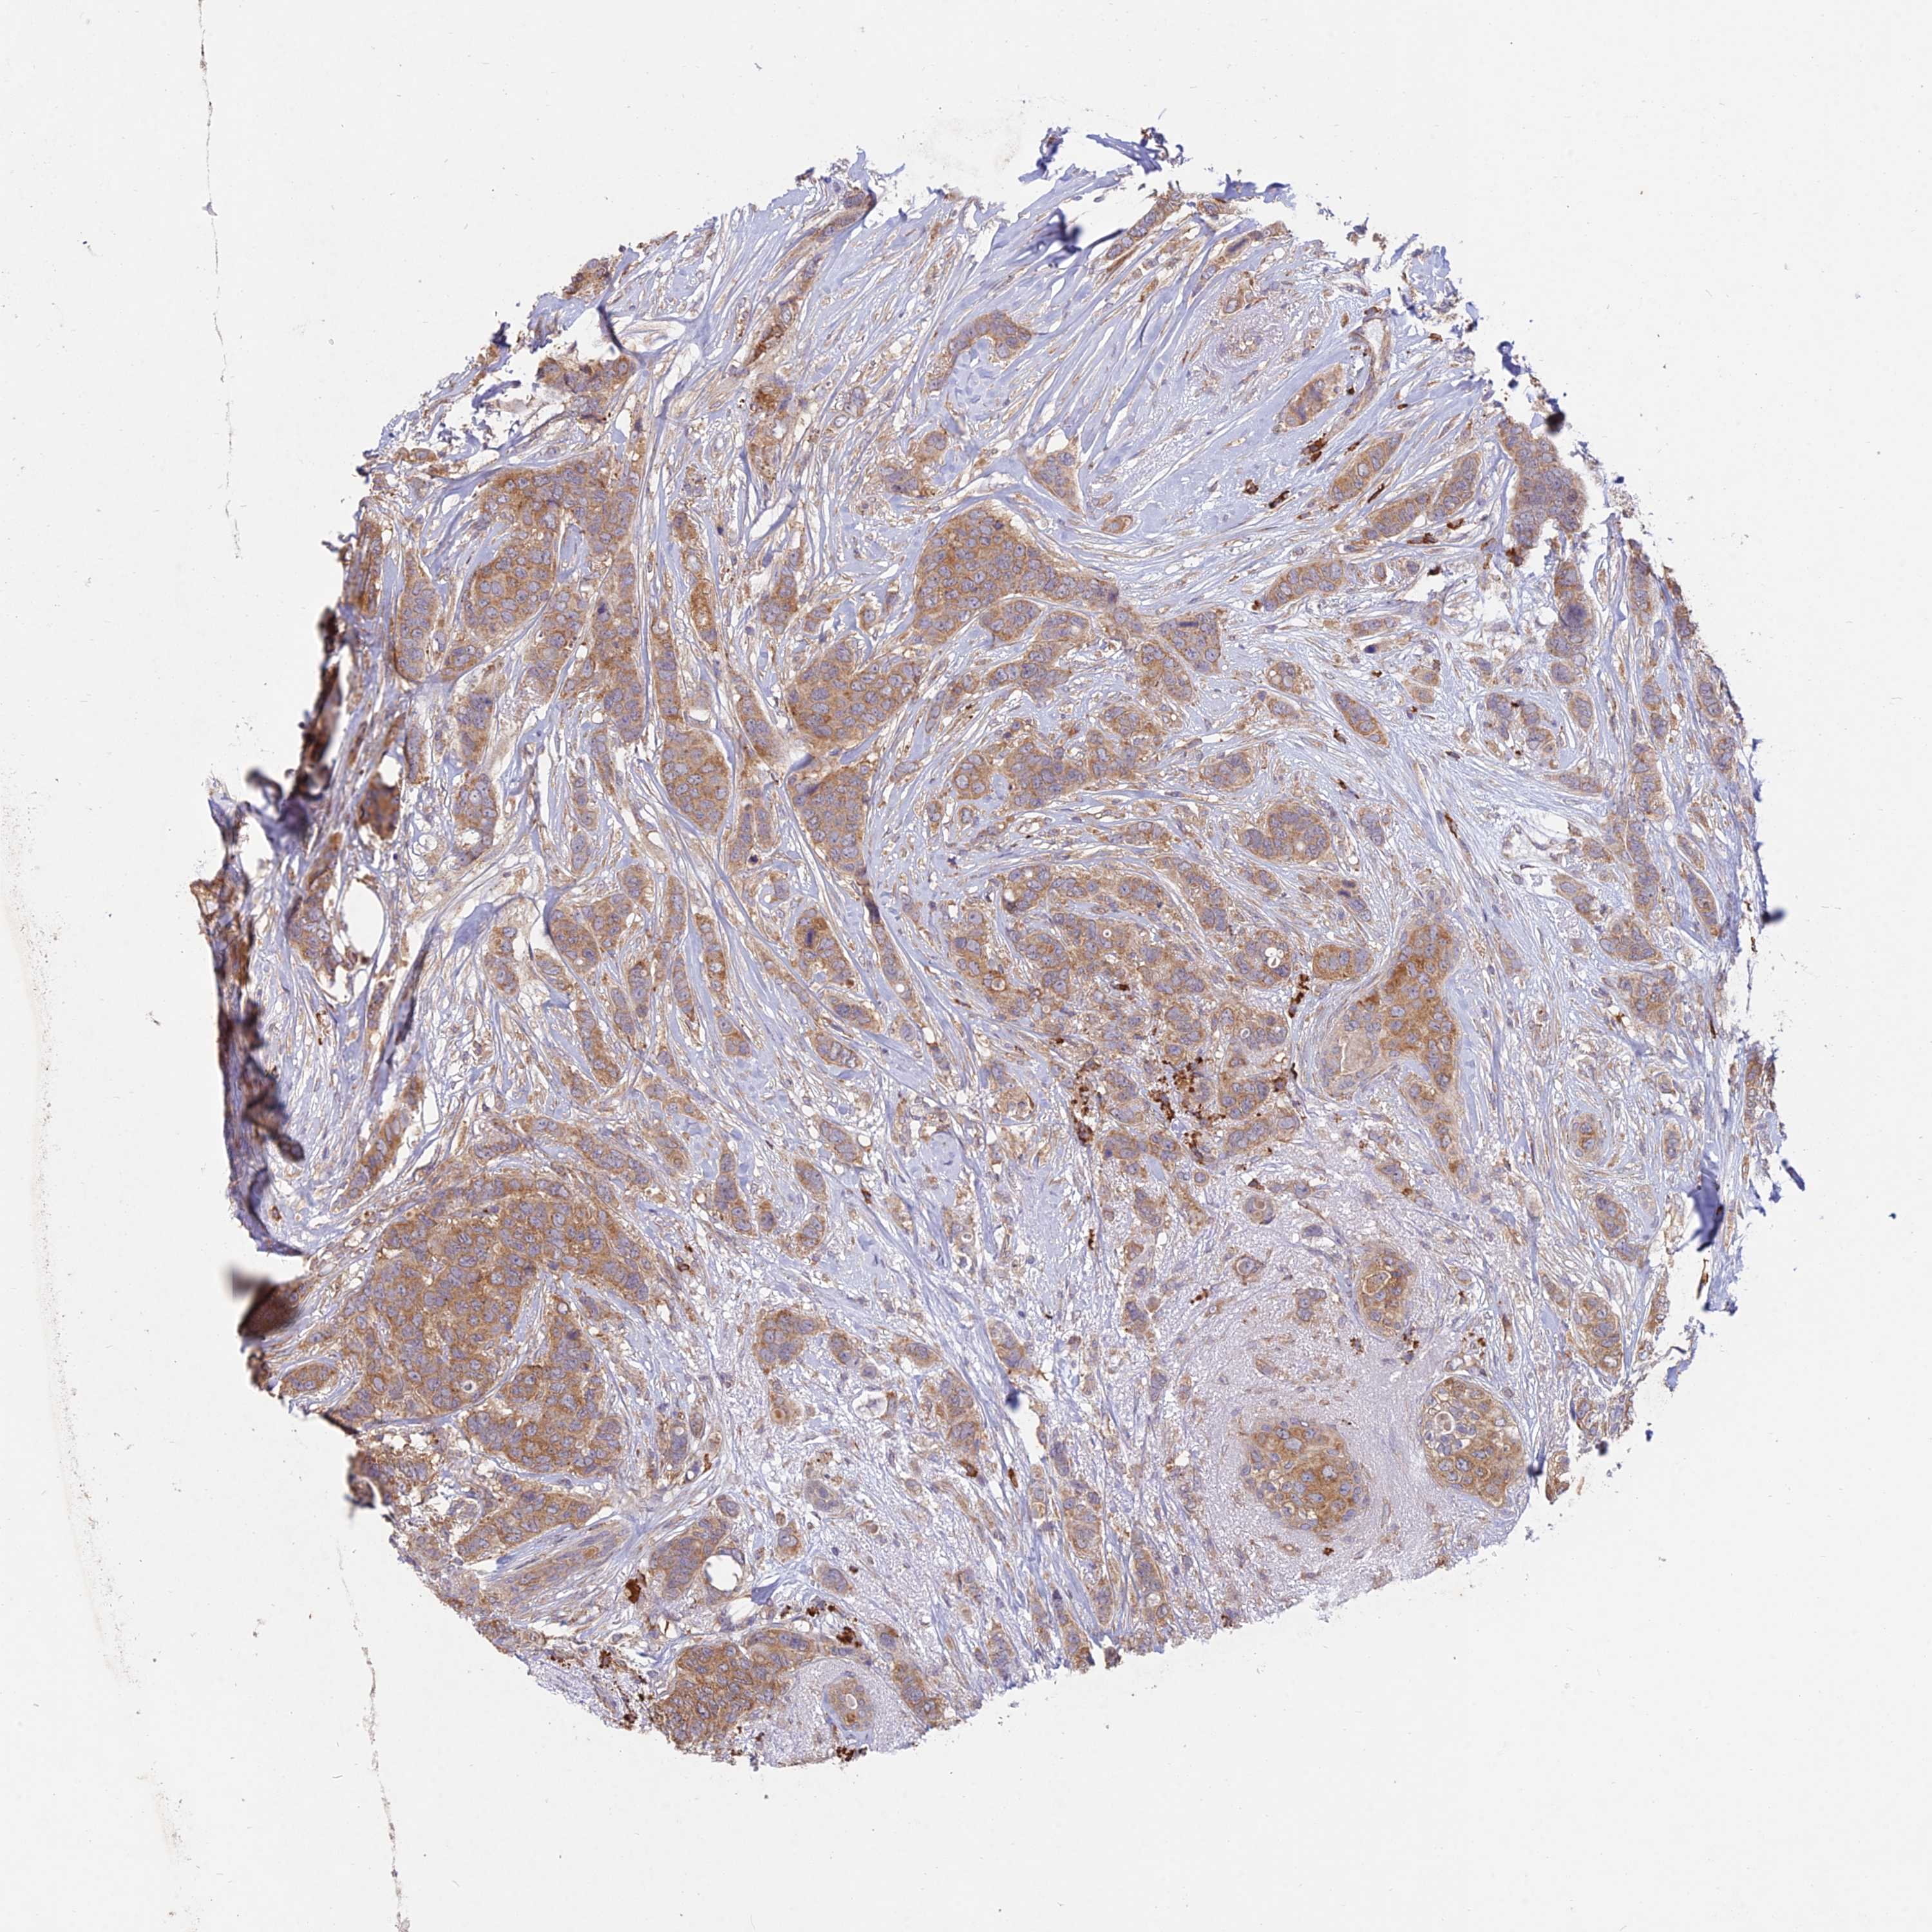

BRCA TCGA BRCA VALIDATION PROTEIN EXPRESSION

ANTIBODIES

AND

VALIDATION